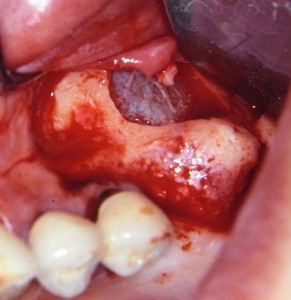

上の臼歯部欠損にインプラントを4本使用したケース。手前の2本(写真上では左側の2本)は、まだ骨造成の概念がなかった時代に埋入したもので、骨が薄くて高さがあるところには細くて長いインプラントを、骨が厚くて高さが無いところには短くて太いインプラントを選択していた(別に今でも問題は生じていないが)。その後、2002年にミシガン大学でサイナスリフトを研修し、副鼻腔内に骨造成を行った後、後ろの2本(写真では右側2本)を追加埋入した。外側に骨を作らなければならないケースに比べて、内側に骨を作るイメージのサイナスリフトは、ある意味ストレスが少ない?だが慢心は禁物である。副鼻腔周囲の骨の厚み、血管の存在、副鼻腔内の骨表面の複雑なケースなどハードルが高いケースはいくらでもある。度重なる研修と経験でさらなる診断力を養いたい。補綴物(被せもの)の精度ももっと上げる必要がある。

サイナスリフト